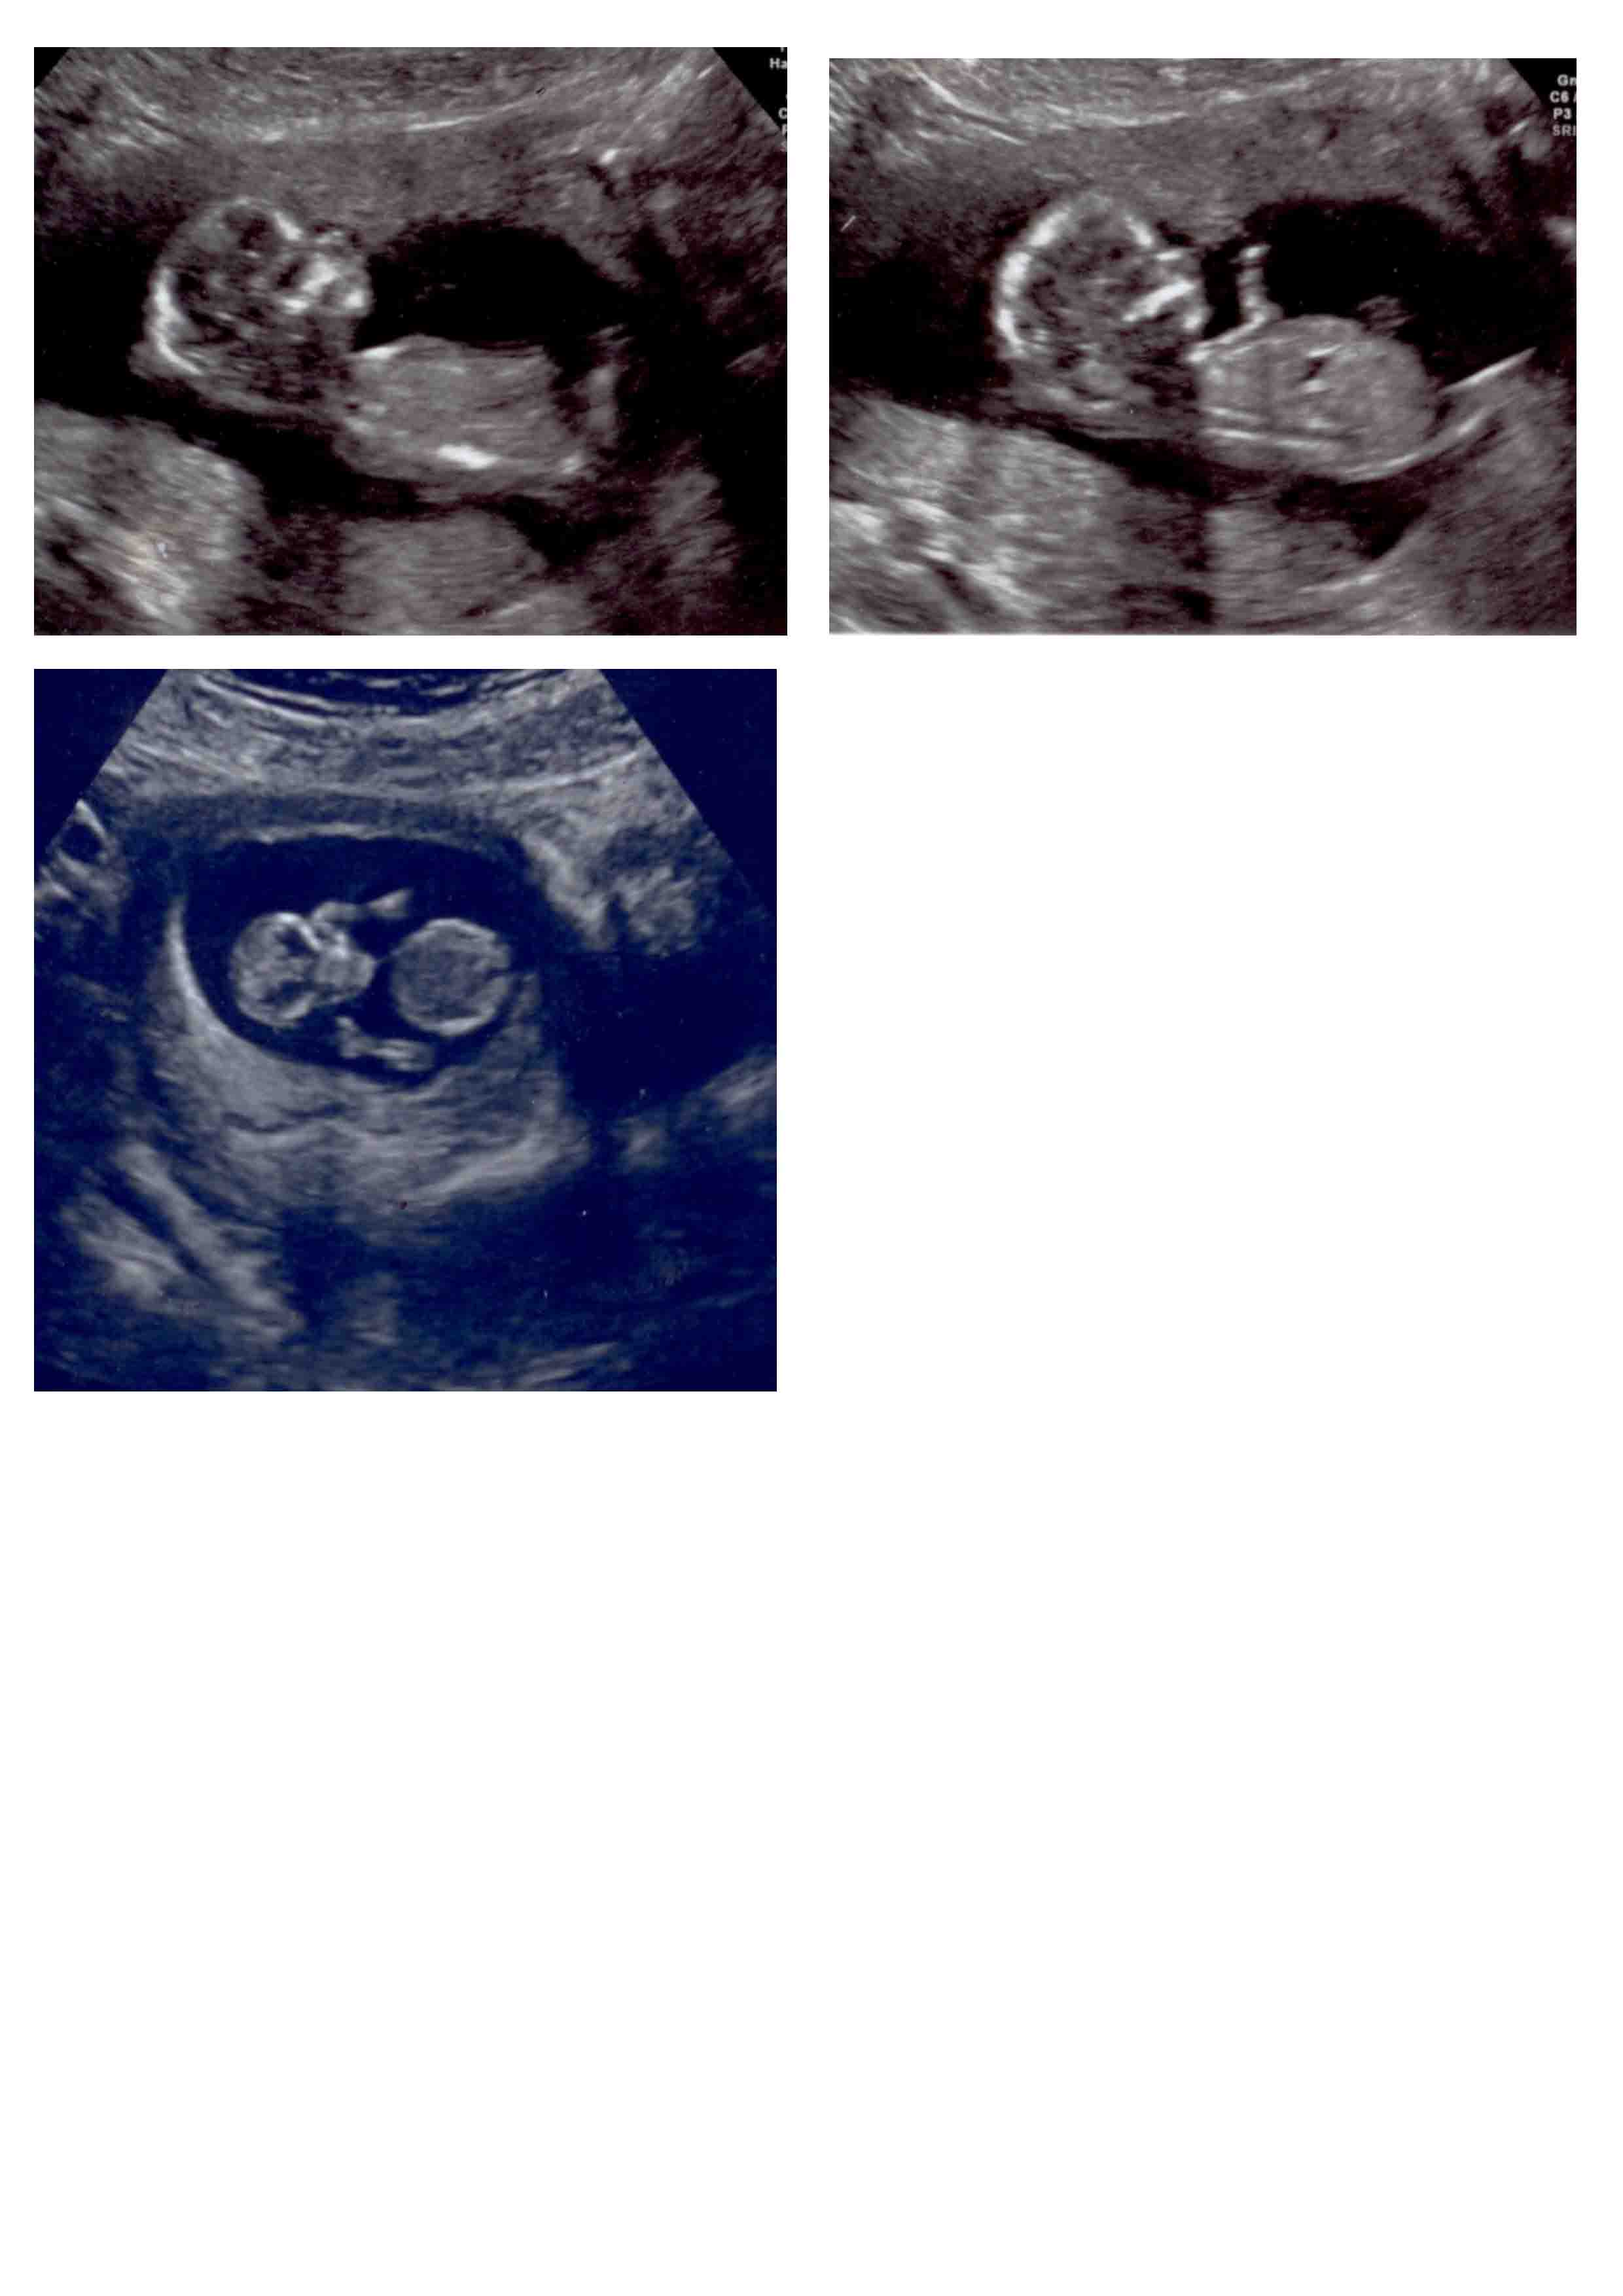

Pleasse have a look and see if you can make a guess - girl or boy :-) xxx

I have had 2 scans so far - one at 12 weeks ( the one face on at the bottom) and the second at 14 weeks (the top 2)

I am desperate to find out if it is a girl or a boy and lots of my friends have had a guess but would love more opinions from the scans if anybody could make a guess from what you can see .......